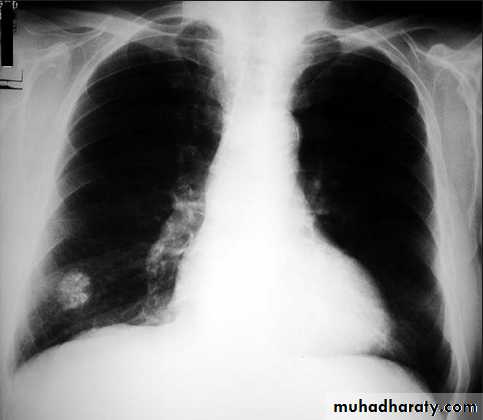

Mycoplasma pneumonia. A 35 year old man presents with nonproductive cough and fever